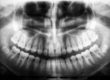

What should you do if an adult tooth is growing behind the baby teeth?

Around the age of 6, children will begin to lose their deciduous teeth and permanent adult teeth will grow into these spaces shortly afterwards. However, sometimes the adult teeth begin to grow in a row behind the baby teeth. This is sometimes referred to as shark teeth in reference to the rows of teeth that sharks have,